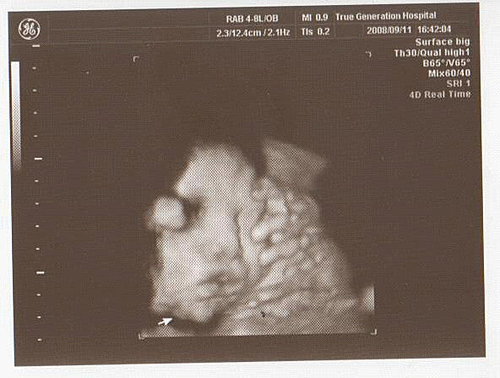

轉4D時

由於寶寶側臉

所以看不到正面

可是看到臍帶繞了脖子一圈

醫生說沒有辦法判斷是緊還是鬆

因此要多留意胎動